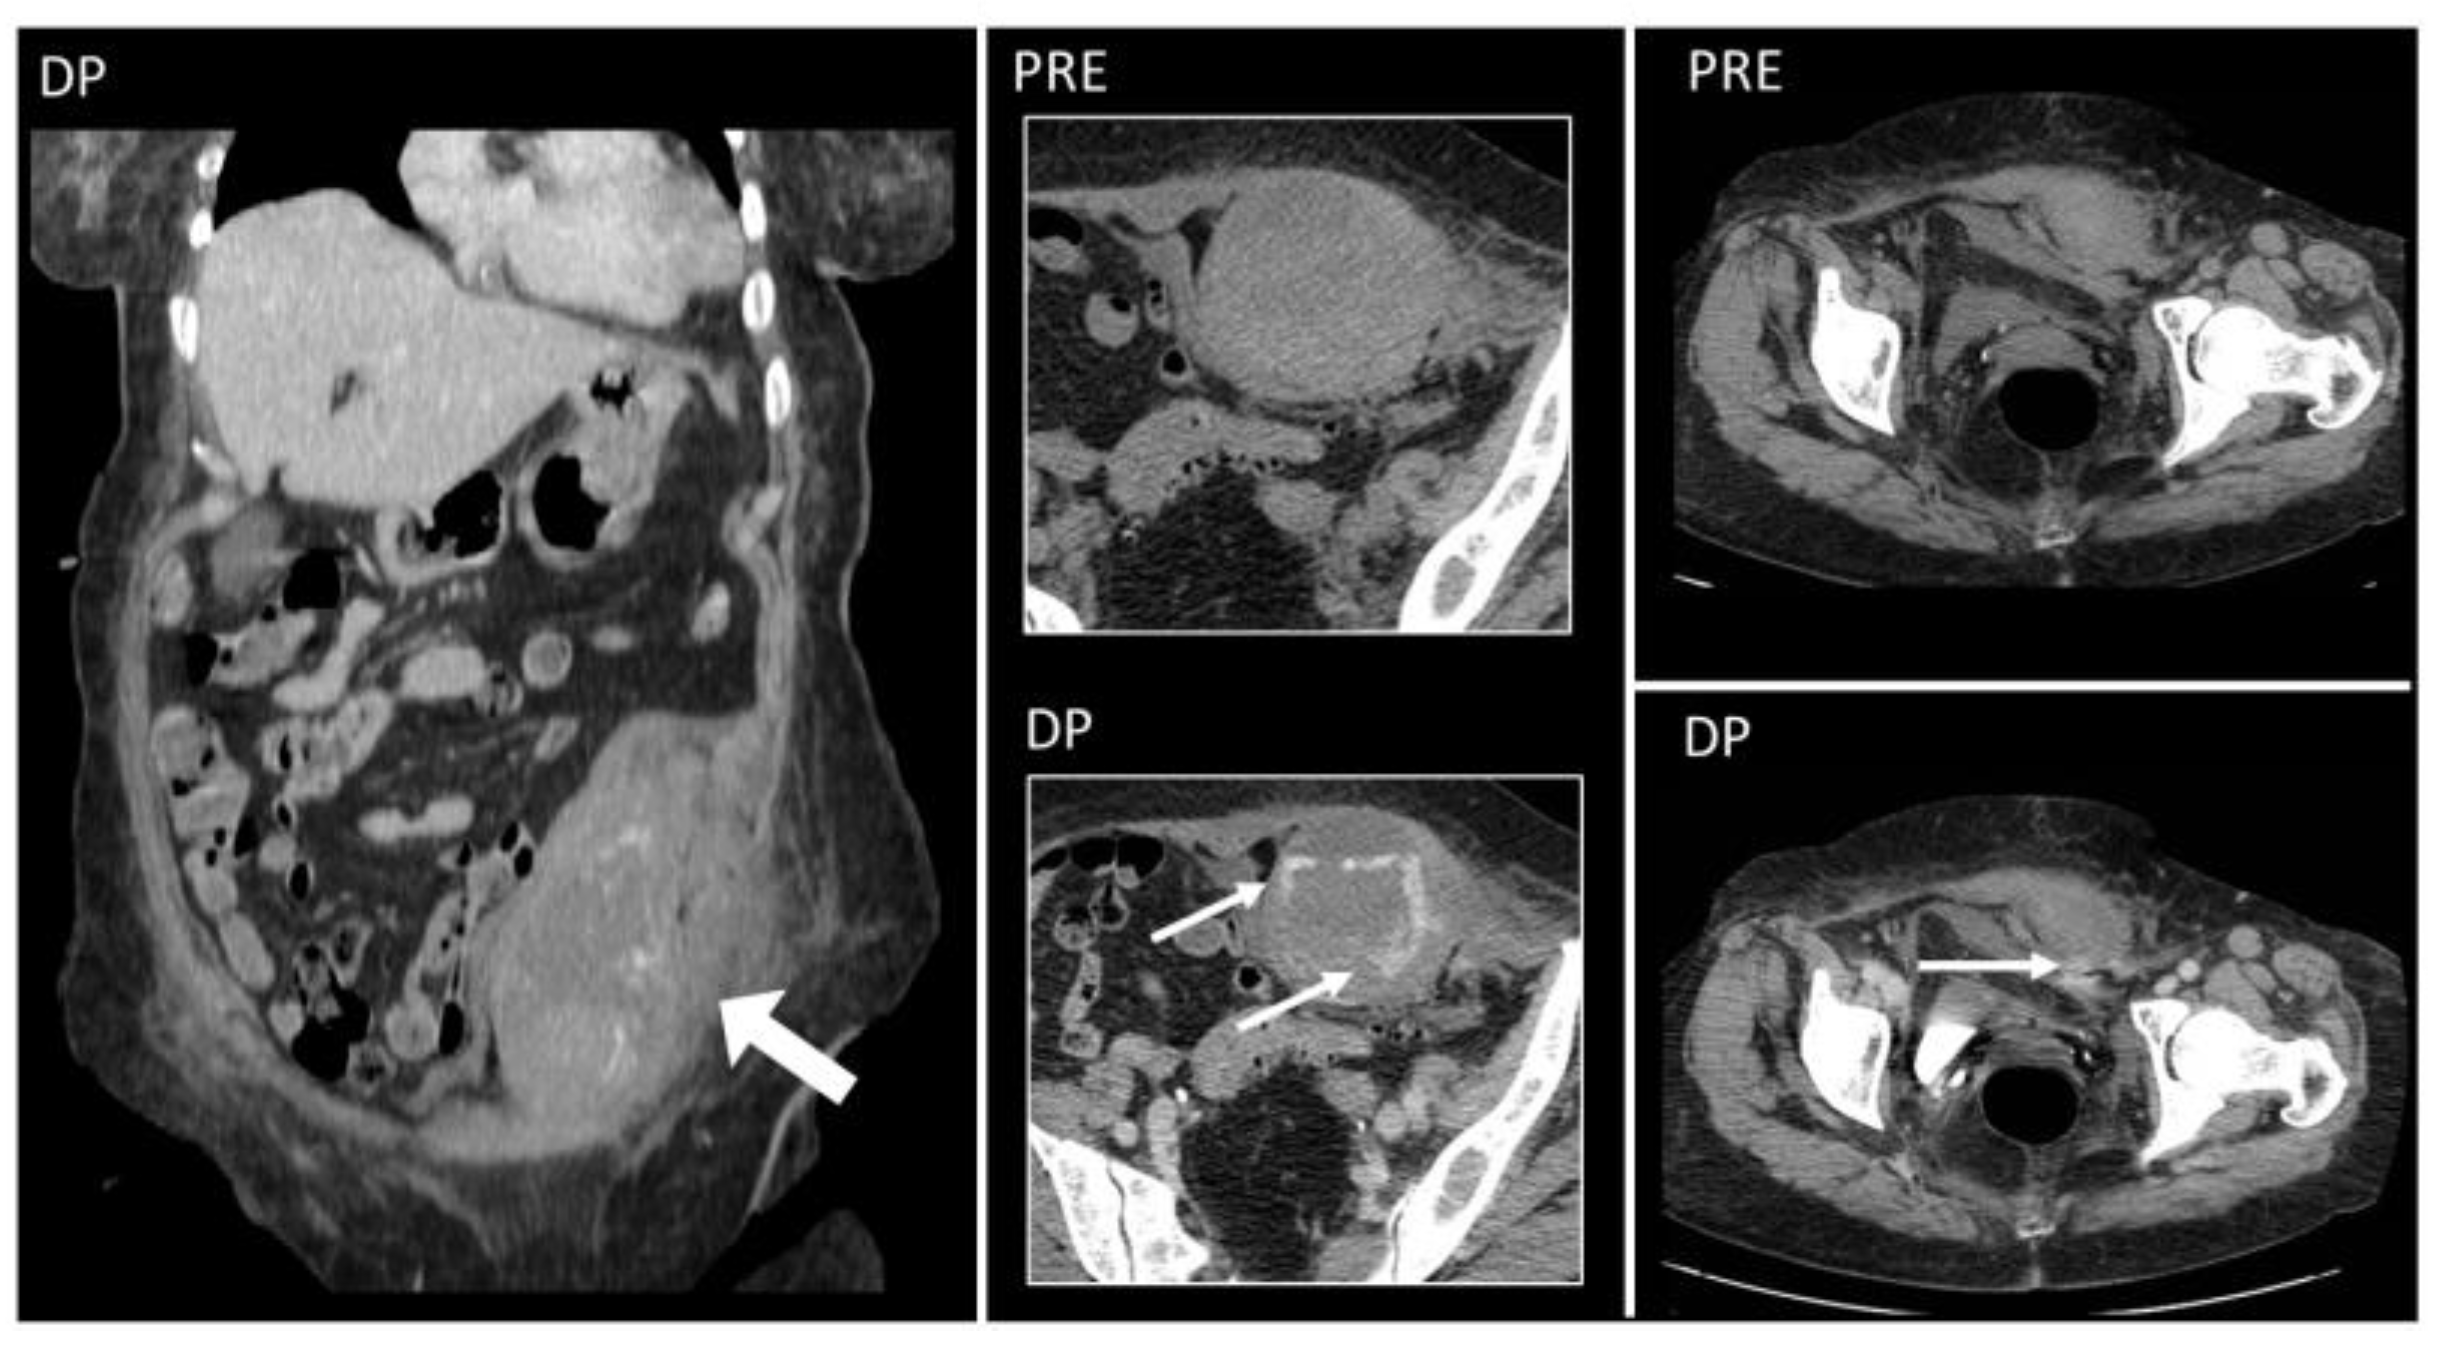

Figure 11. Hematoma below the arcuate line in a 75-year-old woman, with acute myeloid leukemia and low platelet count. After a cough, she started complaining of strong abdominal pain and a mass started growing. Coronal and axial, pre- and post-contrast injection images showed the presence of a large left rectus sheath hematoma (thick arrow) with active arterial bleeding, as demonstrated by the subsequent spreading of contrast in all phases acquired (thin arrows). Since the hematoma was below the arcuate line, bleeding into the prevesical space is also noted (arrow, last picture, bottom row).